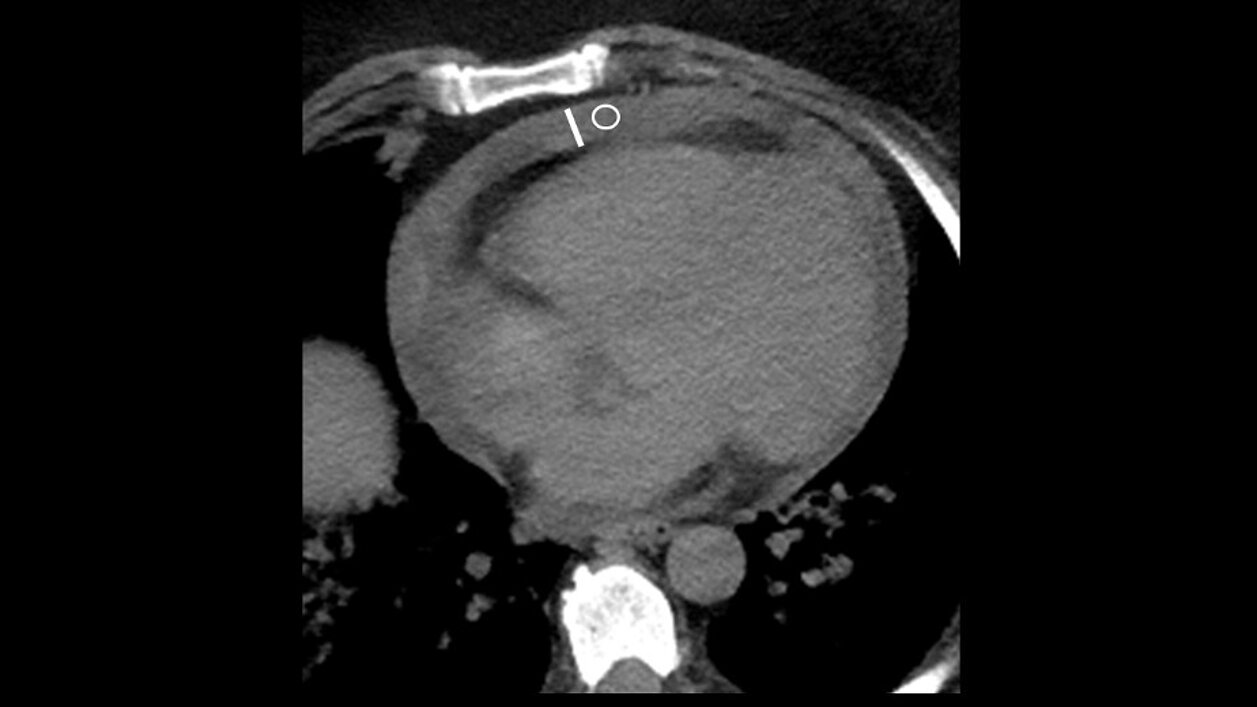

Eine multizentrische Studie [1] im Rahmen des deutschen Forschungsinfrastrukturprojekts RACOON (Radiological Cooperative Network of the COVID-19 pandemic, ein Projekt des Netzwerk Universitätsmedizin) untersuchte die prognostische Bedeutung von Perikardergüssen (PE) in einer Kohorte von COVID-19 Patient:innen.

Die retrospektive Studie umfasste Daten von 1197 Patient:innen mit bestätigtem COVID-19, welches mittels Polymerase-Kettenreaktion (PCR) diagnostiziert wurde. Die Forscher:innen konzentrierten sich auf die Prävalenz des PE, seine Korrelation mit klinischen Ergebnissen und seine prädiktive Rolle für die 30-Tage-Sterblichkeit, die Notwendigkeit mechanischer Beatmung und die Aufnahme in die Intensivstation.

Insgesamt 46,4% der Patient:innen mussten auf die Intensivstation aufgenommen werden, wobei in 26,6% der Fällen eine mechanische Lungenbeatmung durchgeführt wurde. Ein Perikarderguss lag bei 13,3% der Patient:innen vor, wobei dessen Auftreten in Fällen mit tödlichem Ausgang höher war (24% der Patient:innen mit 30-Tage-Mortalität). Bei Nicht-Überlebenden und Patient:innen, die auf die Intensivstation aufgenommen oder mechanisch beatmet werden mussten, war die PE-Häufigkeit höher. Bemerkenswerterweise korrelierte das Vorhandensein von PE nicht mit dem Ausmaß der Lungenschädigung, die mittels CT-Scoring ermittelt wurde (Dichte r = -0,02, p = 0,71 und Breite r = 0,10, p = 0,18).

Die Studie legt nahe, dass der Perikarderguss eine unabhängige Variable für die 30-Tage-Mortalität ist, insbesondere bei männlichen Patienten mit COVID-19 (p-Wert = 0,04). Die Prävalenz von PE war bei männlichen Patienten höher als bei weiblichen (14,7 % vs. 9,9 %, p = 0,051). Die prädiktive Rolle des PE wurde jedoch bei weiblichen Patienten nicht beobachtet.